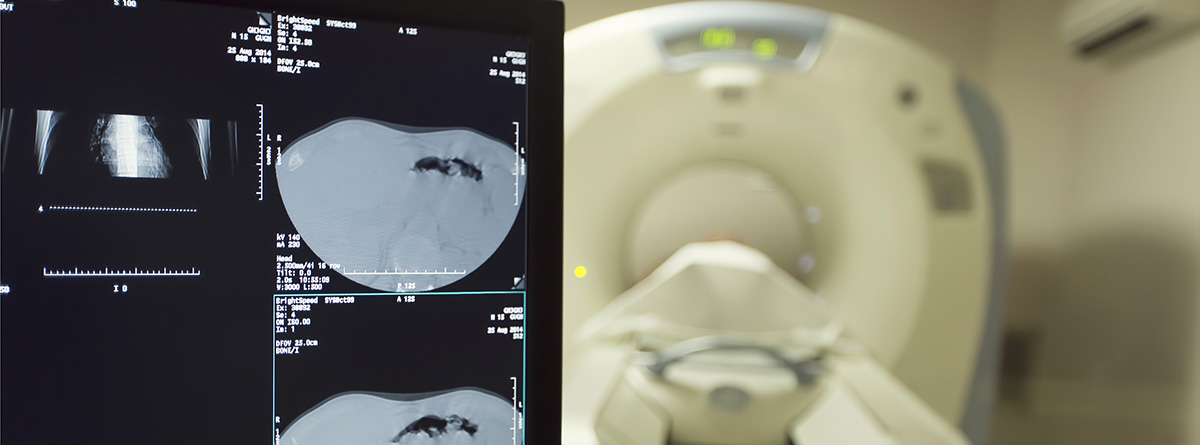

- La gammagrafía ósea es una prueba sensible para la detección de una gran variedad de trastornos óseos como fracturas, infecciones, tumores, artritis y enfermedades óseas metabólicas. Esta prueba es útil para detectar alteraciones en el metabolismo óseo (reabsorción de hueso en el caso del SDRC) y, realizada dentro de los primeros cinco meses después de la aparición de los síntomas, puede respaldar el diagnóstico. No obstante, un resultado negativo no descartaría el diagnóstico de SDRC.

- La radiografía simple tiene una sensibilidad baja. Muestra una patrón de desmineralización del hueso en forma de “parches”. Se puede emplear la extremidad contralateral a modo comparativo.

- Otros métodos como la resonancia magnética nuclear (RMN) o la tomografía computarizada (TC) pueden ayudar al diagnóstico de exclusión de otras patologías, pero no sirven para confirmar el diagnóstico. La TC puede mostrar áreas focales de osteoporosis pero considerando la dosis de radiación, costo y experiencia limitada no suele formar parte del conjunto de pruebas a realizar. Del mismo modo, la respuesta favorable tras una simpaticolisis química (es decir, un bloqueo del nervio simpático) tampoco supone un confirmación de SDRC.